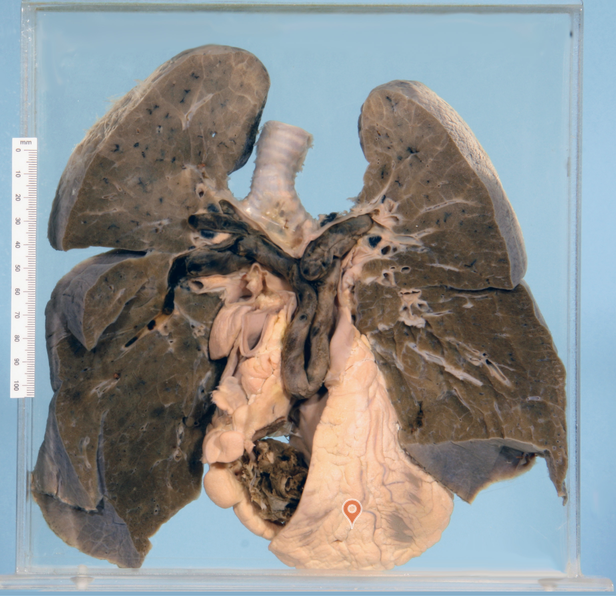

Saddle embolism

Pulmonary embolism and infarction with fibrinous pleurisy